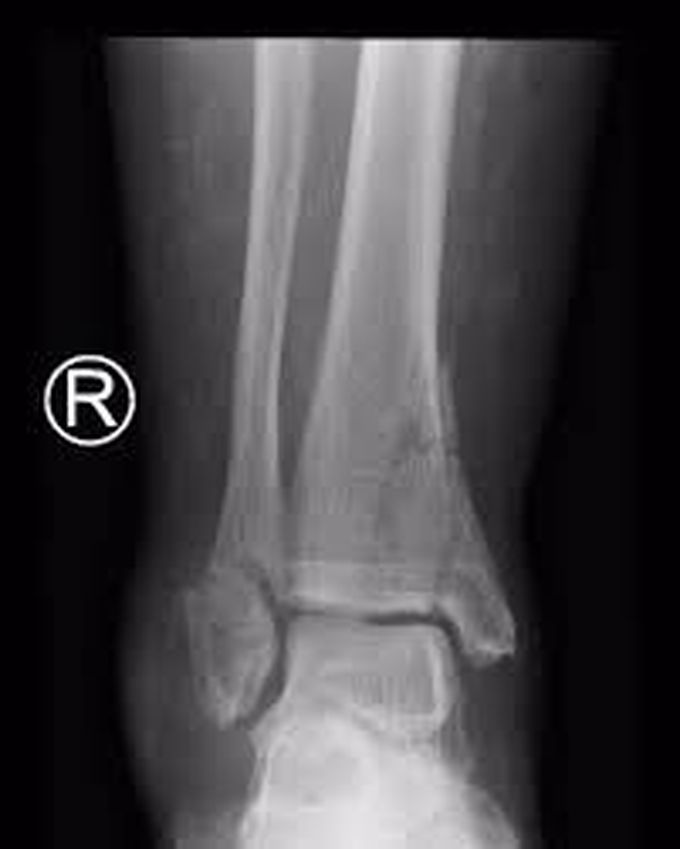

A female patient diagnosed with a 43B2 Pilon fracture. ab

A female patient diagnosed with a 43B2 Pilon fracture. ab How Serious Is A Pilon Fracture Symptoms tend to be severe and include: Pilon fractures are serious injuries. This break usually happens after falls, car accidents, or work accidents. It is common for patients to have residual aches, swelling, stiffness, and weakness. A pilon fracture is a break at the end of the shin bone. You likely won't be able to put weight on your foot.. How Serious Is A Pilon Fracture.